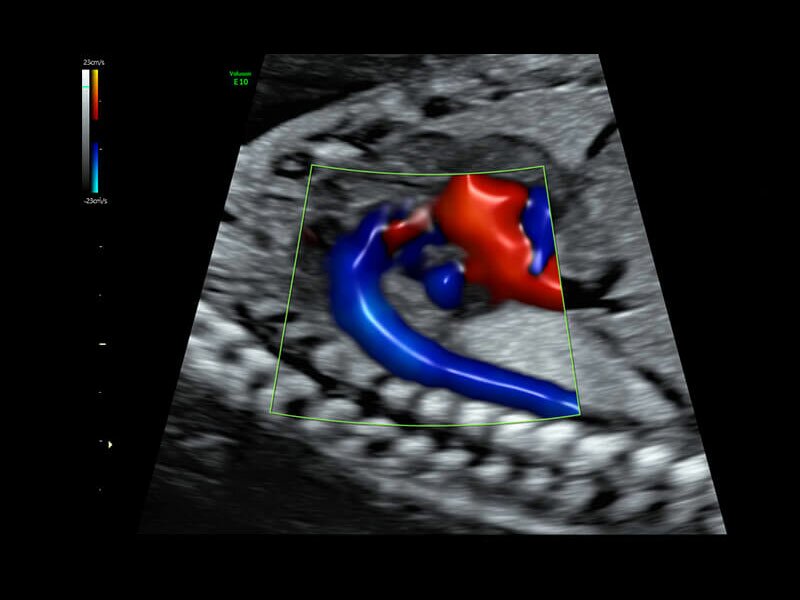

• Высокочувствительный допплер (HD-Flow)

• Реалистичный объёмный кровоток в режиме ЦДК (Radiantflow)

• HDlive Flow - перемещаемый источник света, совместимый с визуализацией кровотока в 3D

• HDlive Flow Silhouette - режим "Силуэт" с выделением границ полостей сердца и сосудов, совместимый с визуализацией кровотока

• Advanced STIC - расширенный программный пакет для исследования сердца плода в режиме 4D для механических и электронных объемных датчиков:

• Использование цветного, энергетического допплера, В Flow - режим STIC.

• Перемещаемый источник света - STICflow

• Технология HDlive Flow — повышает реалистичность визуализации сосудистых структур, улучшая восприятие глубины (по сравнению с традиционным цветовым допплером и функцией HD-Flow).